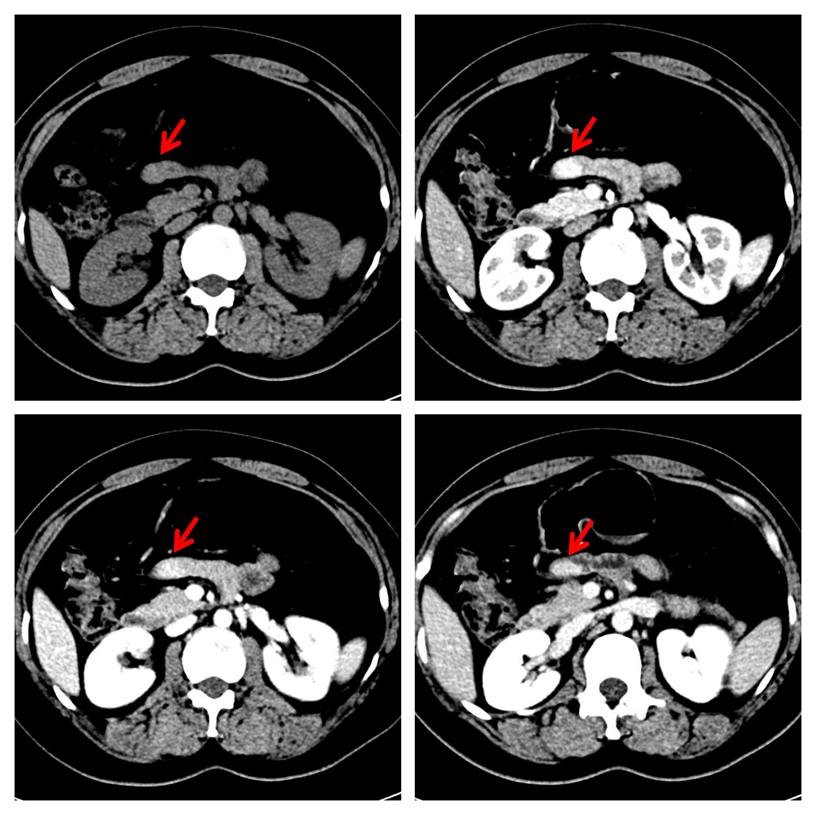

中年女性,2年前因"右胸壁惡性黑色素瘤"行手術(shù)治療,平素?zé)o腹脹、腹痛、惡心、嘔吐等不適癥狀。本次常規(guī)復(fù)查,行增強CT檢查發(fā)現(xiàn)小腸結(jié)節(jié),考慮神經(jīng)內(nèi)分泌腫瘤可能大(圖1)。本次發(fā)病以來,精神、飲食、睡眠差,近2 日有少量便血,小便無異常。體格檢查:腹部平坦,未見腸型及蠕動波,腹肌軟,無壓痛及反跳痛,腸鳴音弱。實驗室檢查:消化道腫瘤標(biāo)志物(甲胎蛋白、癌胚抗原、糖類抗原19-9、糖類抗原72-4)、血常規(guī)、肝腎功能均在正常范圍內(nèi)。

圖1,增強CT檢查示小腸結(jié)節(jié)(紅箭),明顯強化